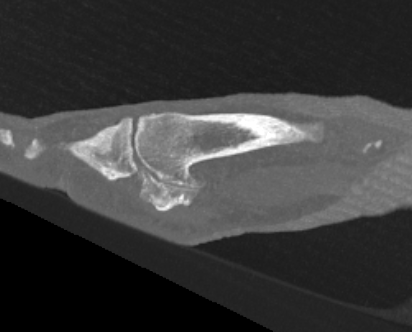

X-ray

Osteoarthritis

- joint space narrowing

- dorsomedial osteophyte

Severe OA

- removal of dorsal osteophytes

- increase painless dorsiflexion range

Remove ~ 1/3 of dorsal metatarsal head

- remove osteophytes from base of P1